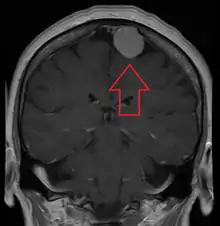

Meningiomata are visualized readily with contrast CT, MRI with gadolinium,[18] and arteriography, all attributed to the fact that meningiomata are extra-axial and vascularized. CSF protein levels are usually found to be elevated when lumbar puncture is used to obtain spinal fluid. On T1-weighted contrast-enhanced MRI, they may show a typical dural tail sign absent in some rare forms of meningiomas.[15]